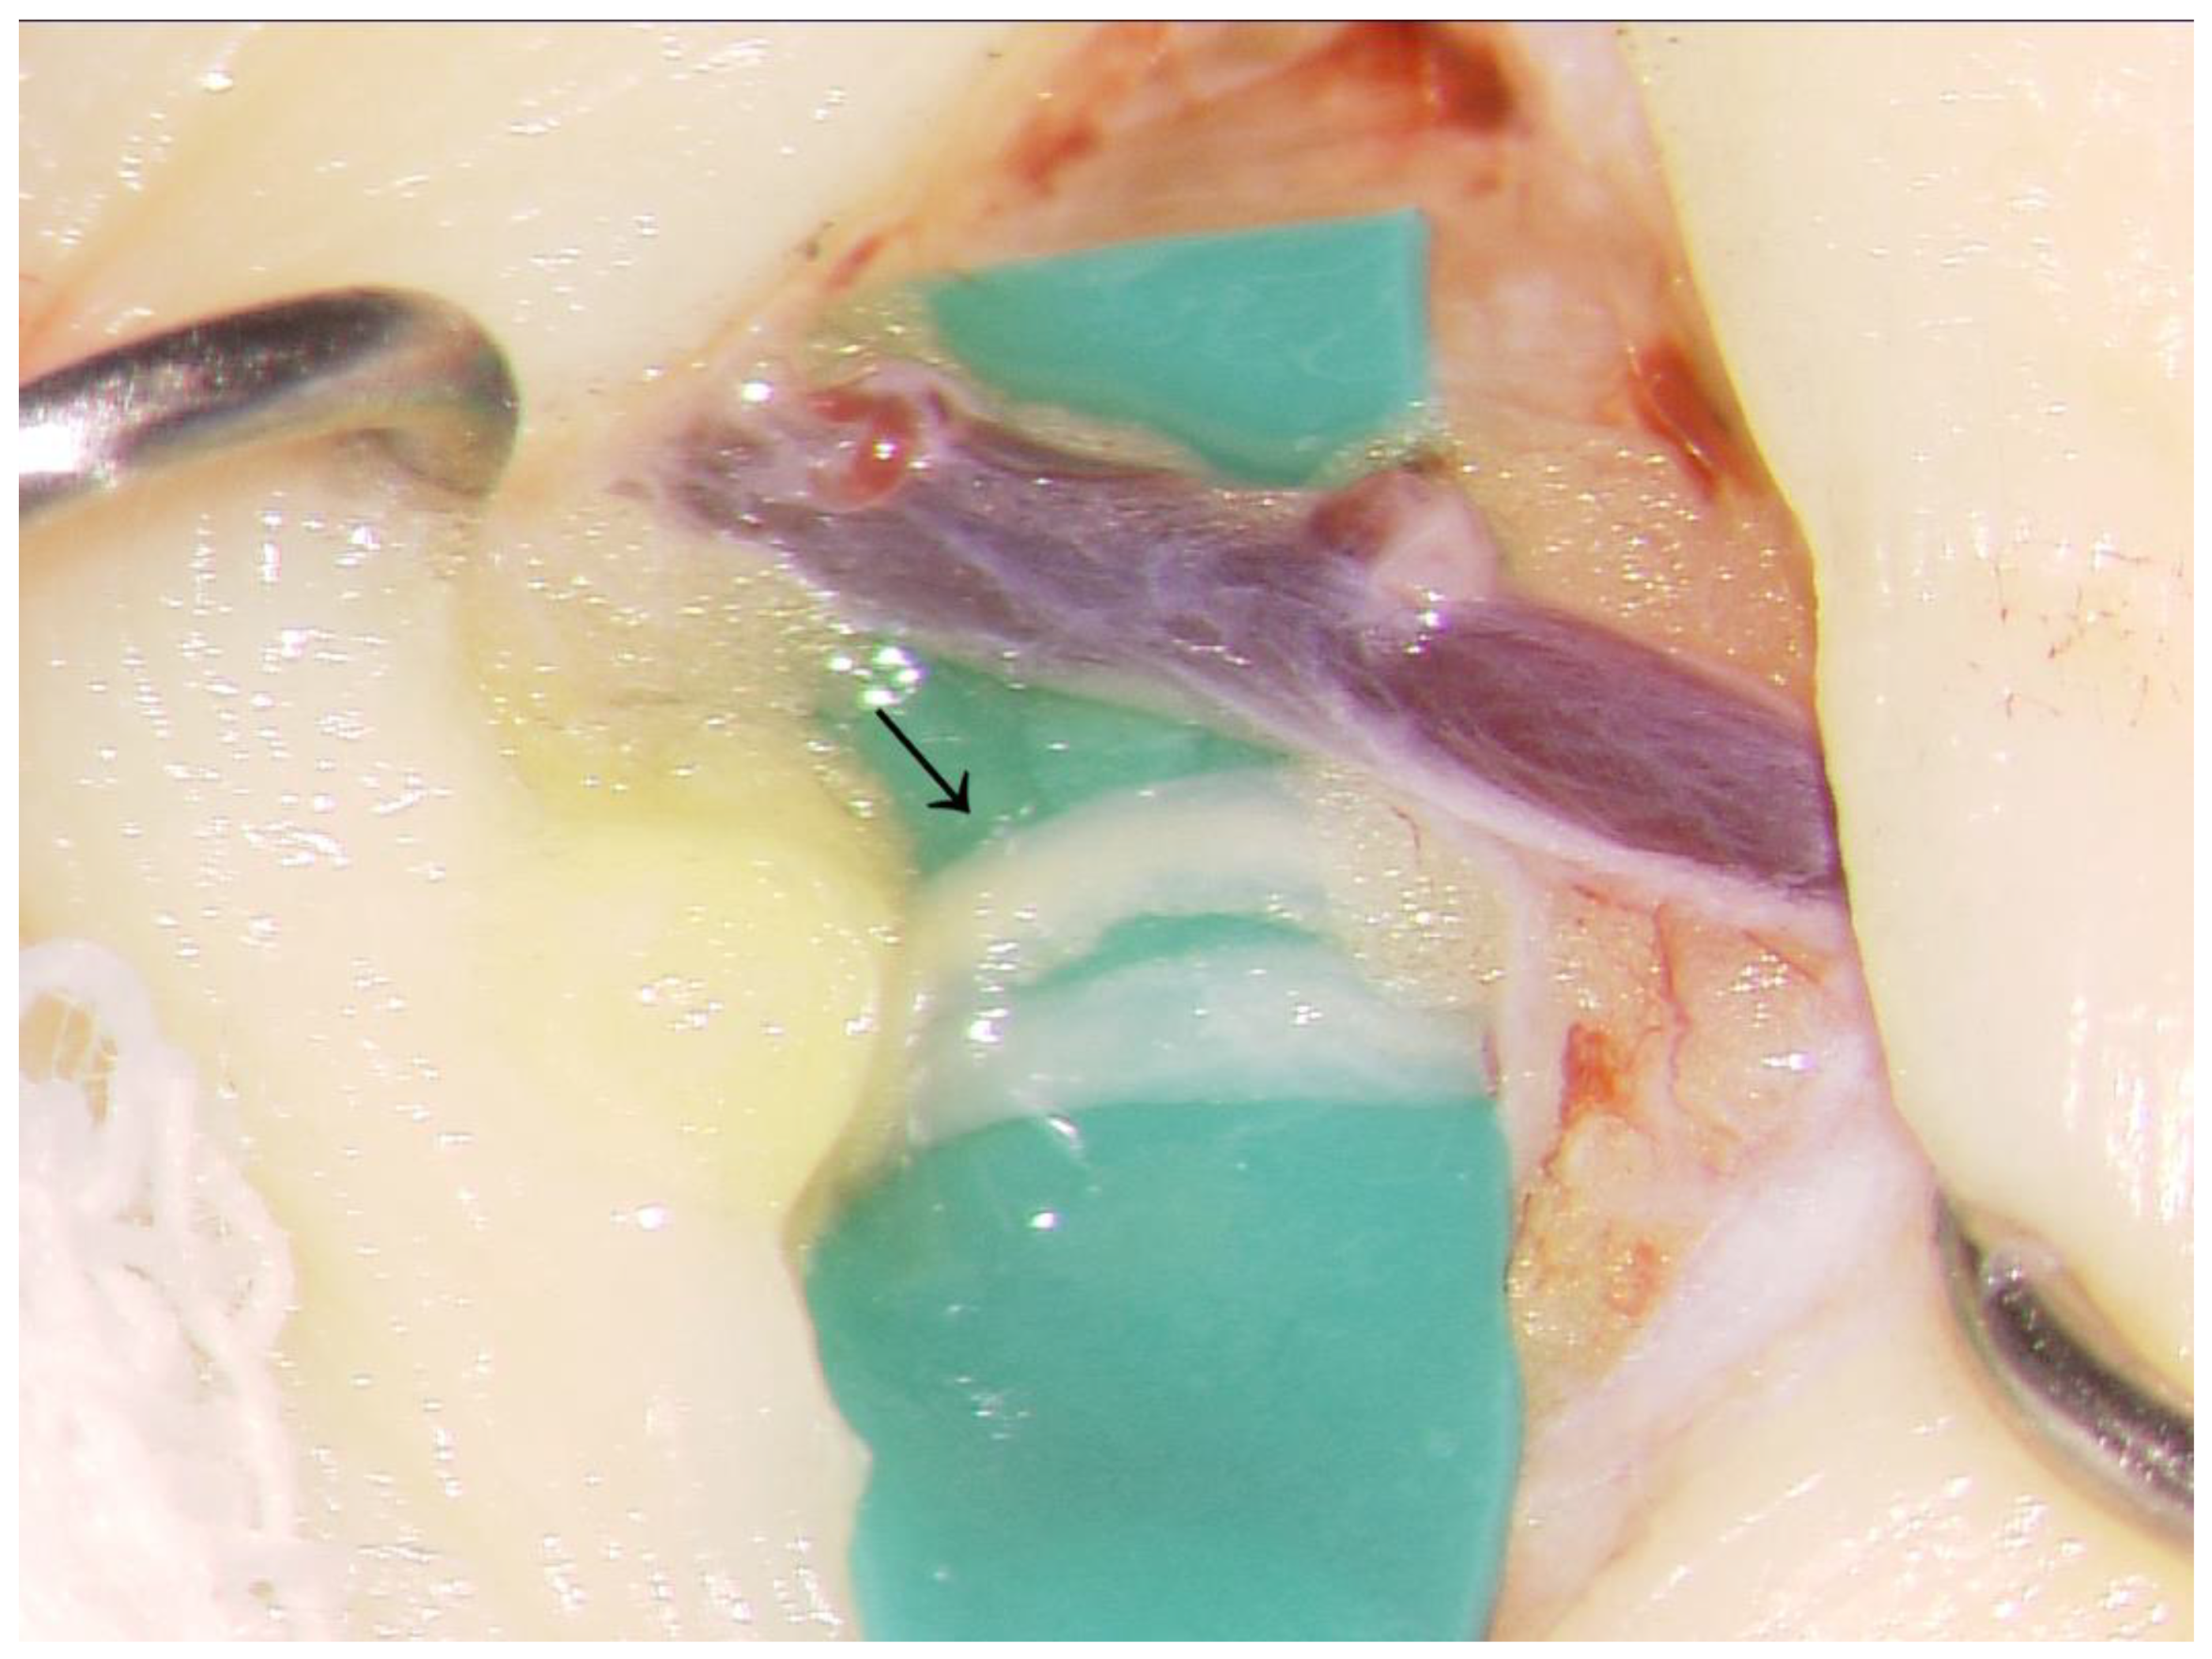

2.1. Surgical Procedure